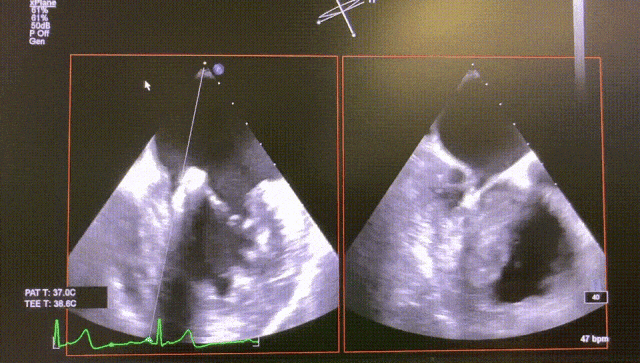

Case1

The patient is a 72-year-old female with mitral valve P3 prolapse and severe mitral regurgitation. After evalsuation, the patient was suitable for transcatheter mitral edge-to-edge repair (TEER) using the DragonFly™ system.

The procedure was uneventful, with only one XW0612 mitral clip implanted in P3 position to close the leaflet. The patient's regurgitation decreased with pulmonary venous regurgitation improved, and the mitral valve pressure difference was 1 mmHg, significantly improving the patient's cardiac function.

Before

After